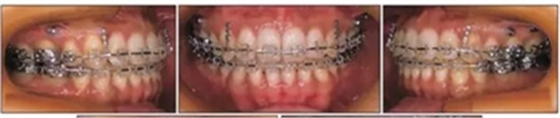

然后拔除下頜第二前磨牙,開始綜合正畸治療,解除前牙擁擠,并通過遠(yuǎn)中移動上牙列獲得I類磨牙關(guān)系(Figure 7)。